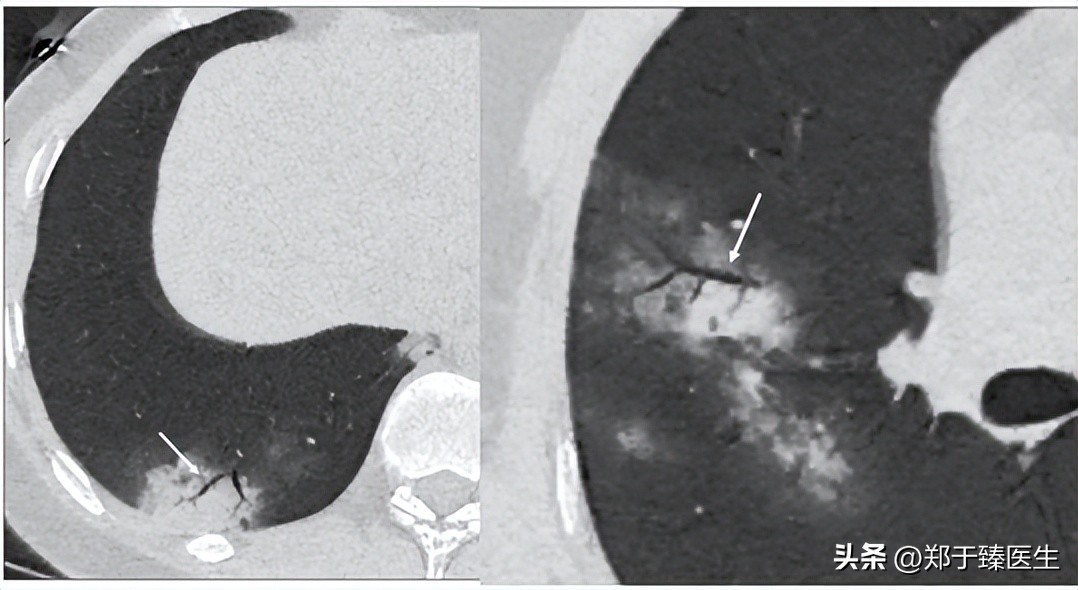

12月下旬,患者联系我,说自觉胸闷不适,我担心体内遗留肺炎情况,因此建议他复查了个CT(2022.12.25),结果一看,果然出现肺炎了。

于是,我尽快给他安排住到我们医院,在和主管医生沟通后,查了核酸阴性,于是就上了小剂量激素配合抗生素进行处理(2022.12.26开始)。

一周后,复查CT,炎症消退,患者症状明显好转,办理出院(2023.1.4)。

前后治疗周期10天。

从CT的片子来看,炎症几乎全部吸收,甚至连胸膜下线都没有看到,这说明实变区域吸收非常彻底,没有遗留任何纤维结缔组织,也就是没有任何后遗症。

下面就是治疗前后的CT改变: